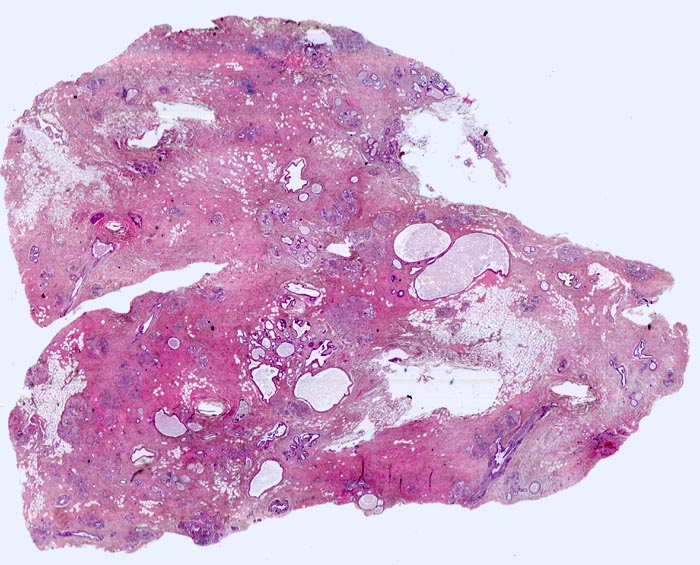

Ausgedehnte Fibroseareale schliessen kleine Inseln von Fettgewebe ein. Zahlreiche Gänge sind unterschiedlich stark dilatiert. Zusammen ergibt sich die Diagnose einer fibrös zystischen Mastopathie.

Probeexzision wegen umschriebenen Mikroverkalkungen in der Screeningmammographie. Bei der Palpation lassen sich mehrere unscharf begrenzte derbe Knoten tasten.